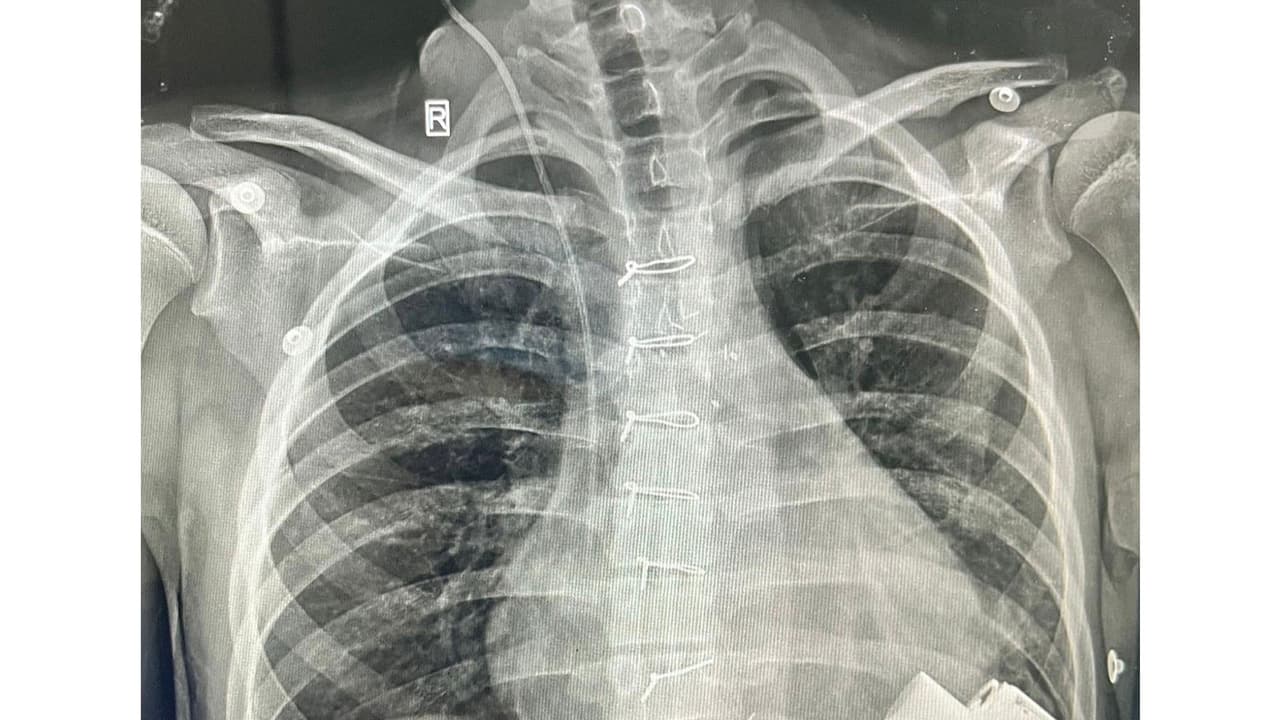

A 14-year-old child from Uzbekistan, Dilshod, had been living with dilated cardiomyopathy for almost ten years. This is a condition in which the heart muscle becomes very weak, making it difficult for the heart to pump blood to the various parts of the body and ultimately causes 'Life-Threatening Heart Failure'. This 14-year-old boy is now the first child to be discharged in northern India after receiving a Mechanical Heart - a Left Ventricular Assist Device (LVAD). He is now also the youngest recipient of an LVAD device in India. This pioneering surgery was performed at the Department of Pediatric Cardiac Surgery at a Private Hospital in Gurugram.

Over the past year, his illness had gotten worse, with advanced heart failure that severely limited his ability to do simple day-to-day activities- even getting out of bed and walking a little would make him short of breath. Every couple of weeks, he would need hospitalisation in the ICU to control his heart failure, and since 'No Treatment' was available for this end-stage heart condition in his home country, doctors suggested that they should either seek treatment at an advanced centre in India or prepare for an unfortunate eventuality. His parents brought him to Artemis Hospital in Gurgaon, about two months back, where he was put on the waiting list for a Pediatric Heart Transplant. His condition was getting worse by each day that passed and over the past 2 months he has been admitted FOUR times because of Heart Failure, to the Pediatric Cardiac ICU at Artemis Hospital and once this was with 'Cardiogenic Shock' where his organs (Liver, Kidneys) started to shut down and fail because the heart could not pump enough blood to these organs. At this point it was clear that he would probably not survive the waiting time needed for a donor heart to be available for transplant and so after discussion with the family doctors at the Department of Pediatric Cardiac Surgery, Artemis Hospital decided to do something that has not been done for a child of this age, in India- Implant an 'Artificial Heart Pump- LVAD; to save his life.

After a complex and difficult surgery that involved connecting a Mechanical Heart Pump to the main pumping chamber of the heart and then connecting the other end (outflow) to the Aorta - the artery that takes blood to various organs of the body. The whole pump is so small that it sits inside the chest and connects to a computerised controller and battery through a small wire that comes out of the skin. As the device was started, it pumped blood from the left ventricle to the body and within a few days in the Pediatric Cardiac ICU, his organ functions started recovering.